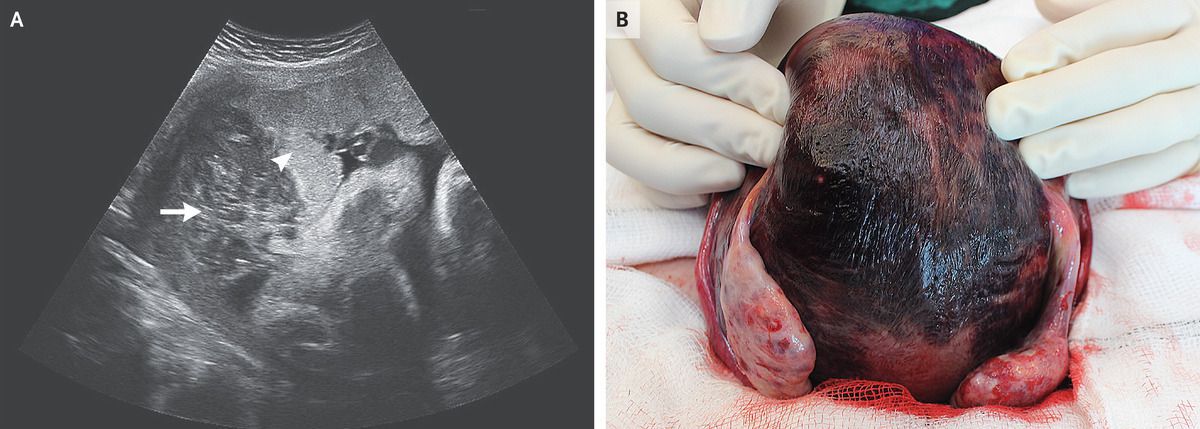

A 29-year-old primigravid woman presented to the labor and delivery unit with contractions at 33 weeks 3 days of gestation. She had had no recent vaginal bleeding, ruptured membranes, or abdominal trauma. A physical examination was notable for a firm and tender uterine fundus. Transabdominal ultrasonography revealed retroplacental hemorrhage (Panel A, arrow; arrowhead shows the placenta), and a fetal heart-rate tracing showed a nonreassuring pattern with deep variable decelerations. An emergency cesarean section was performed. Intraoperatively, the uterus appeared bruised owing to the extravasation of blood into the myometrium, a condition known as a Couvelaire uterus (Panel B). The patient received a diagnosis of concealed placental abruption, which refers to the premature separation of the placenta resulting in hemorrhage that is contained between the detached placenta and the uterus. Affected patients thus do not present with vaginal bleeding, and there is a risk of intrauterine fetal death or hypoxic brain injury if the diagnosis is delayed. The newborn’s 1-minute and 5-minute Apgar scores were 8 and 9, respectively. After delivery, the uterus was atonic, and the patient received treatment with carbetocin, oxytocin, misoprostol, and tranexamic acid. Her postoperative recovery was uncomplicated, and the baby was discharged after hospitalization for prematurity.